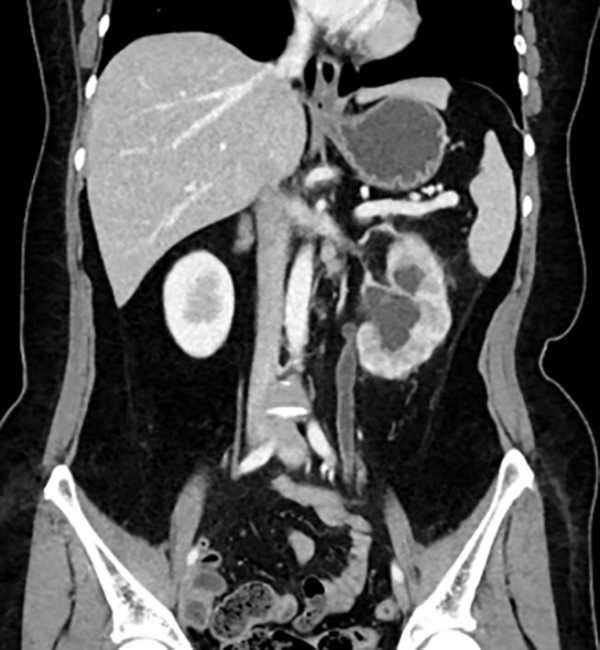

王女士术前CT

术后半年复查积水缓解